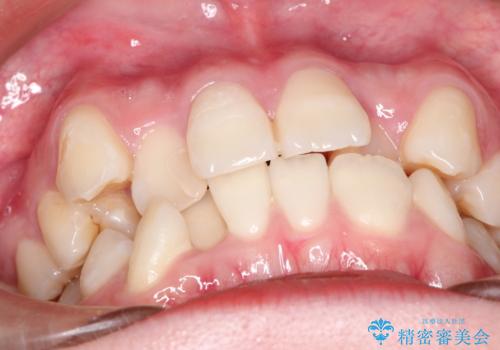

八重歯のワイヤーによる抜歯矯正 矯正治療と並行してセラミック治療も

- 八重歯と前歯のガタガタを主訴に来院されました。

ブリッジを除去して、左下以外の上顎両側と右下の歯を合計3本抜歯して矯正する計画としました。